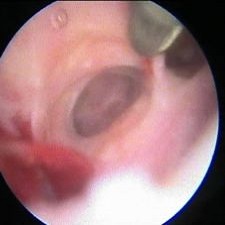

Rozrušení srůstů v dutině děložní

Srůsty v děloze mohou být příčinou různých potíží, např. neplodnosti nebo potratu (i opakovaného). Zmenšují totiž prostor v dutině děložní. Na snímku jich je vidět hned několik, z toho srůst v levé části je plošný, další v pravé části snímku přepažuje dělohu pevným můstkem, před ním je vidět operační nástroj. Teprve za těmito srůsty prosvítá zbývající část dutiny děložní rozdělená na několik tunelů, v nichž by případné těhotenství mělo velmi omezenou možnost se normálně vyvíjet. Hysteroskopie vyloučí tuto anatomickou příčinu, ev. lze srůsty při výkonu rozrušit.